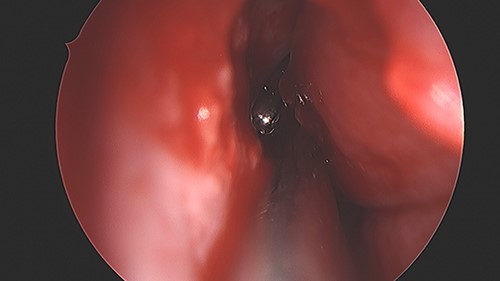

An 11 year-old male was transferred to the emergency room after being shot with a BB gun while playing. The patient’s custodian reports that he returned home with severe bleeding from bilateral nostrils which spontaneously resolved. The patient denies postnasal drip or salty taste. His medical history includes bipolar disorder and attention-deficit disorder managed with medications. On physical examination, an entry point wound is noticed in the skin of the left nasal sidewall (Figs 1 and 2). No active bleeding is noticed from anterior nasoscopy or in the posterior oropharynx exam. The rest of the head and neck examination is unremarkable. Plain X-rays performed in the emergency room confirm the presence of a metallic object in the right nasal cavity/paranasal sinuses (Figs 3 and 4). After consent is obtained, the patient is taken to the operating room and nasal endoscopy is performed. The left nasal cavity appears unremarkable. In the posterior nasal cavity, minimal bleeding and avulsed tissue is noticed after medialization of the middle turbinate. After minimal removal of tissue with pediatric Blakesley forceps, the BB bullet is visualized as lodged in the right posterior nasal cavity adjacent to the posterior attachment of the middle turbinate (Fig. 5). The bullet was then grasped with Takahashi forceps and removed after minimal endoscopic dissection (Fig. 6). Following extubation, the patient was observed for 8 h prior to discharge. During this period, no signs of recurrent epistaxis or cerebrospinal fluid rhinorrea were noticed.